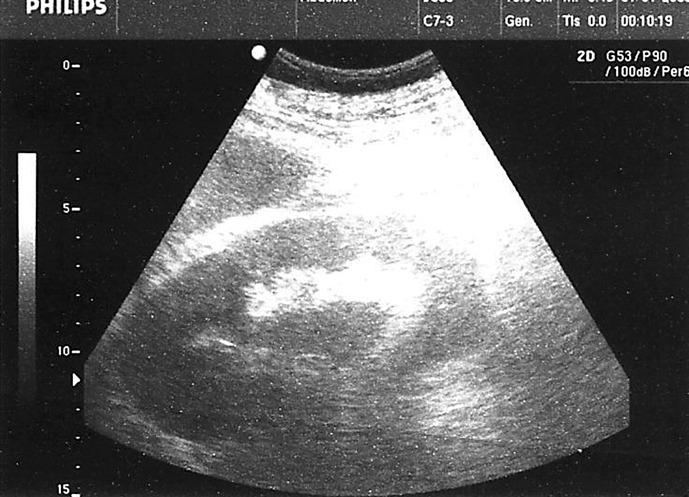

导言:气肿性肾盂肾炎是一种罕见但可能危及生命的尿路感染,其特点是在肾实质、集合系统和肾周组织中形成气体。这种疾病通常发生在有特定易感因素的患者身上,如糖尿病、先天性或后天性梗阻性尿路病或服用免疫抑制剂的患者。在极少数情况下,有其他易感因素(如使用 SGLT2 抑制剂)的患者也会发病,但这种情况并不常见。与使用 SGLT2 抑制剂相关的尿路感染发生率仍有待商榷,但医学文献中已描述了与 SGLT2 抑制剂相关的气肿性肾盂肾炎病例:病例介绍:我们介绍了一例罕见的气肿性肾盂肾炎患者,该患者服用 SGLT2 抑制剂,但没有该病的典型危险因素:尽管使用 SGLT2 抑制剂后发生尿路感染的频率相对较低,但其广泛应用于治疗多种具有重大社会意义的疾病,强调了专科医生有必要了解与使用该药物相关的所有潜在风险,包括发生严重尿路感染的风险。

Introduction: Emphysematous pyelonephritis is a rare but potentially life-threatening urinary tract infection characterized by the formation of gas in the renal parenchyma, collecting system, and perinephric tissue. The condition typically develops in patients with specific predisposing factors such as diabetes mellitus, congenital or acquired obstructive uropathies, or individuals taking immunosuppressive agents. Rarely can the disease occur in patients with other predisposing factors, such as the use of SGLT2 inhibitors, but this is quite uncommon. The incidence of urinary tract infections associated with their use is still debatable, but cases of emphysematous pyelonephritis associated with SGLT2 inhibitors have been described in medical literature.

Case presentation: We present a rare case of a patient with emphysematous pyelonephritis without classical risk factors for the disease, who was taking an SGLT2 inhibitor.